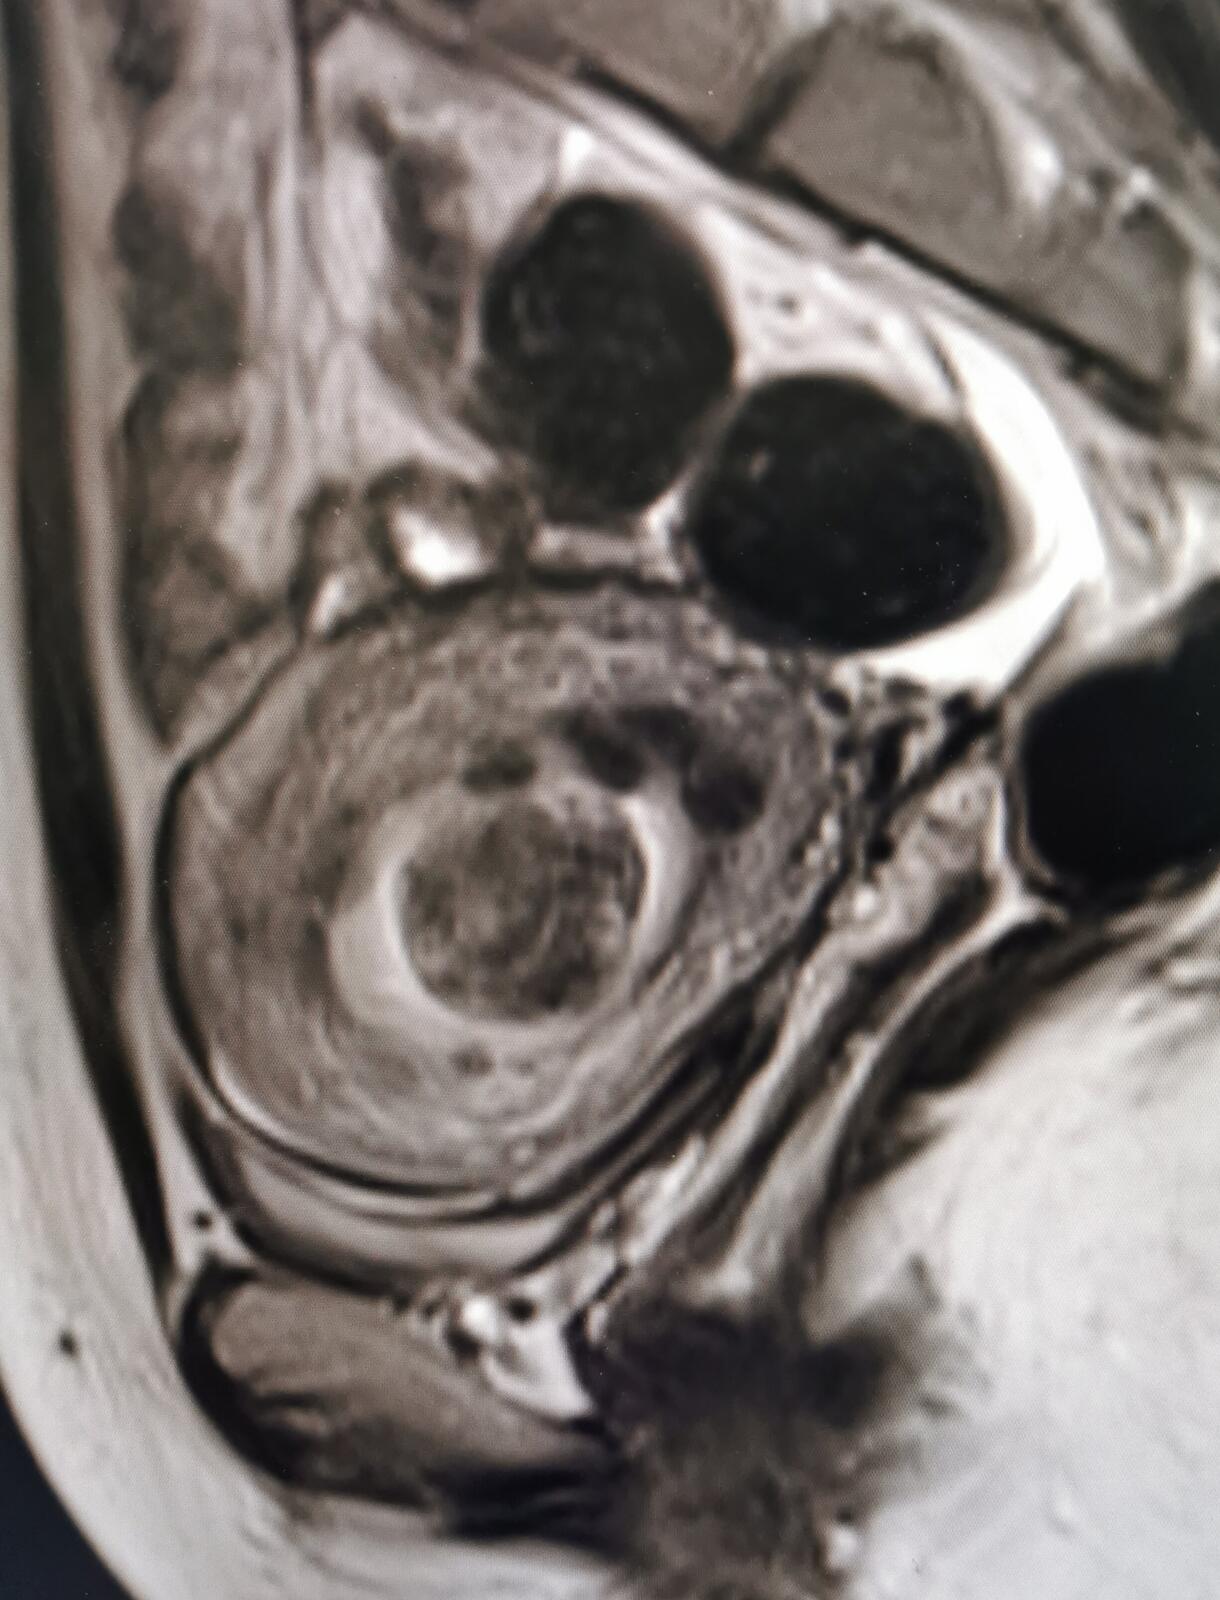

其次综合评估子宫肌瘤大小、位置、数量、位置、磁共振信号和强化特征,这些是确定下一步制定治疗策略的依据

26岁女性,子宫肌瘤治疗前进行磁共振评估,发现有十几个大小不一的子宫肌瘤,很多位于粘膜下,比较大的有蒂,那么宫腔镜一次很难做完,引起宫腔粘连的可能会大一些